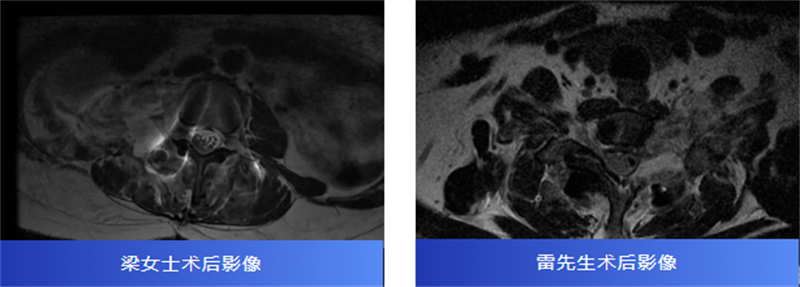

41歲的雷先生(化名)也因為左頸肩部反復酸脹痛了一年多而備受困擾。頸椎磁共振顯示,他的頸椎椎間孔區(qū)域有一個腫瘤,跨越椎管內(nèi)外,明顯壓迫著神經(jīng)。嘗試了多種治療,效果都不理想,疼痛持續(xù)加重。

兩名患者轉(zhuǎn)診至柳州市人民醫(yī)院后,脊柱外科主任、主任醫(yī)師胡巍博士迅速組織醫(yī)學影像科、麻醉科等多學科會診。團隊對腫瘤病變范圍、與神經(jīng)的毗鄰關(guān)系進行周密評估,為每位患者制定個體化手術(shù)方案。

術(shù)中,在顯微鏡輔助下,醫(yī)生精細分離腫瘤與神經(jīng)組織,小心翼翼解除壓迫,最終切除了腫瘤。病理報告也帶來好消息:兩人均為良性神經(jīng)鞘瘤。

術(shù)后,梁女士的腰腿痛消失了,雷先生的頸肩脹痛也得到了緩解。兩位患者都保住了正常的神經(jīng)功能,步入康復的新階段。